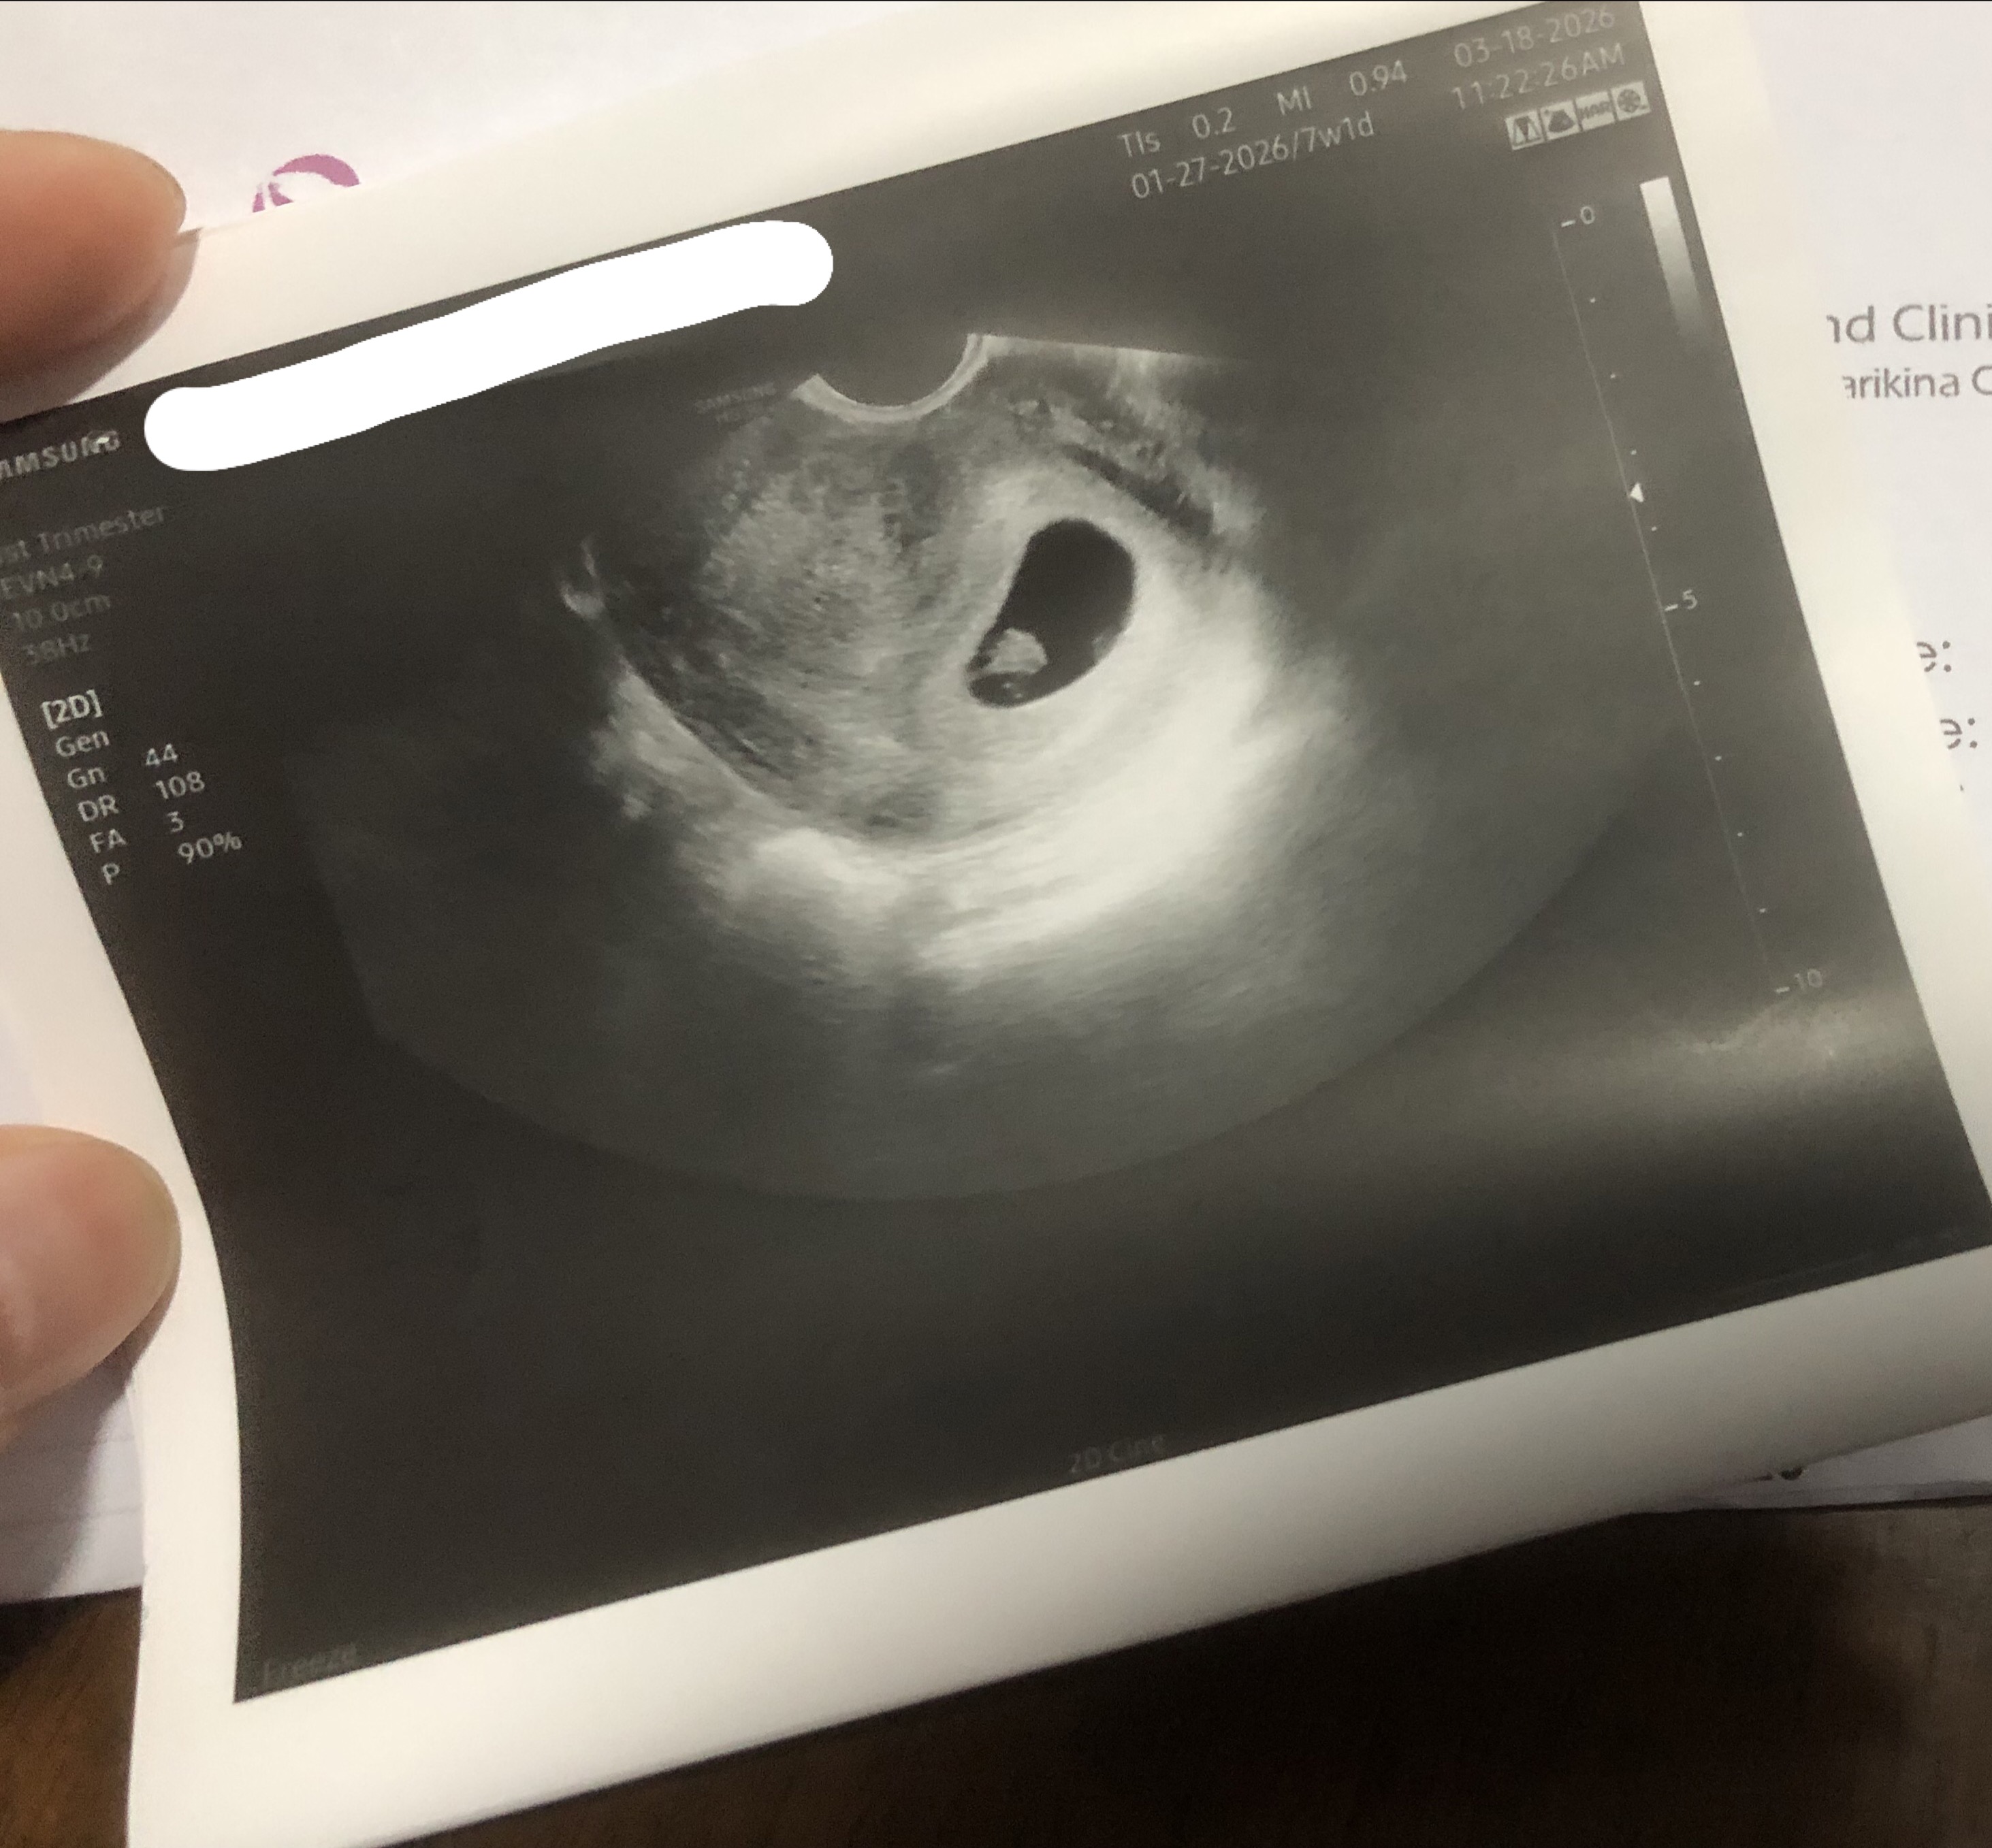

Finally, ultrasound confirmed!

Hello sa mga virtual ninang na nag aabang ng update! 👋 Nakapag ultrasound na kami today, and yes we have a healthy little baby 🥹🫶🏼 7 weeks pa lang kami. Please continue to pray for us 🙏🏼😘